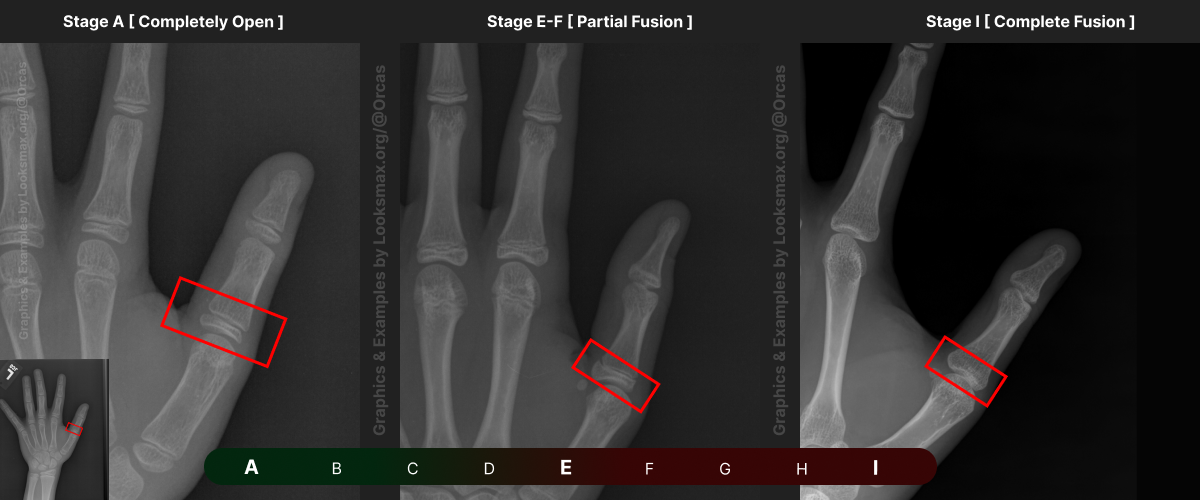

I added references for stages A (Completely unfused), E-F (Partial fusion, basically late stages of puberty), and I (Complete Fusion)

You will have to eyeball this now using your own xrays, I’ve given three examples and some wiggle-room for letters using a reference bar (green-red) below the image, write down your estimated guesses in a text file until you finish all 13 bones.

Don’t doubt yourself, eyeballing isn’t perfect but it still works well, just choose & continue.

Ex.

“My Radius looks more fused than the image from E-F, but its not as fused as I, it’s closer to the 2nd picture though, so I’ll rate it G” And continue

Bonetype: 1st Metacarpal (thumb)

Check & use the chart below to figure out where you are. Then write your result on a piece of paper or a text file.